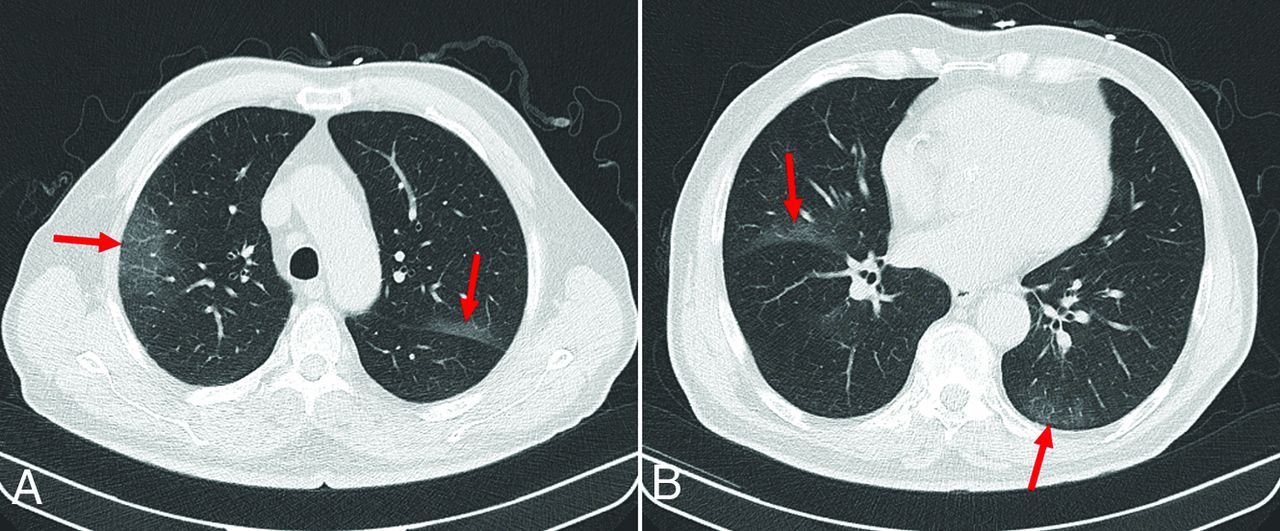

An 83-year-old male patient who underwent head CT for suspected stroke. This patient had symptoms of possible COVID-19 infection (cough and shortness of breath). Axial chest CT images at the level of the aortic arch (A) and heart (B) show ground-glass opacities posteriorly and peripherally, located in both upper lobes (arrows in A and B) and in the left lower lobe (arrow, B). These CT features were interpreted as typical for COVID-19 pneumonia, which was confirmed by RT-PCR.